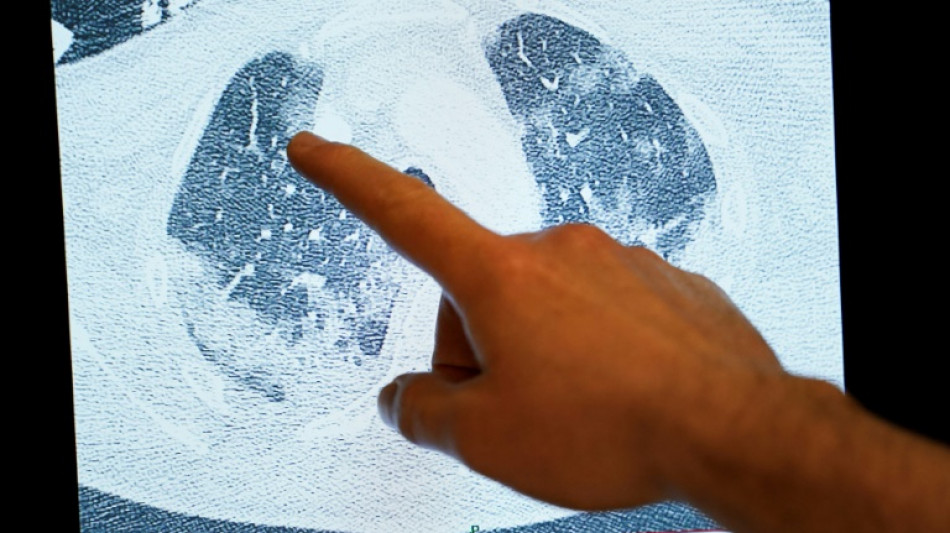

Ce travail se base sur des IRM réalisées chez 259 patients ayant été hospitalisés pour Covid en 2020-2021. Elles ont été comparées avec des examens effectués chez une cinquantaine de personnes jamais infectées.

Près d'un tiers des patients Covid présentaient des "anomalies" dans plusieurs organes, plusieurs mois après leur sortie de l'hôpital. Ces organes incluent notamment le cerveau, les poumons ou les reins et, dans une moindre mesure, le cœur et le foie.

Les chercheurs ont, par exemple, recensé des lésions de la substance blanche du cerveau, un phénomène qui peut être associé par la littérature scientifique à un léger déclin cognitif.

Pour les auteurs de l'étude, ainsi que des observateurs indépendants, ces résultats ouvrent une piste d'explication au Covid long, c'est-à-dire la persistance de séquelles durables plusieurs mois après l'infection.

L'étude rendue publique vendredi laisse penser que le Covid long "ne s'explique pas par des insuffisances graves concentrées sur un seul organe" mais plutôt "une interaction entre au moins deux anomalies de (différents) organes", avance le pneumologue Matthew Baldwin, qui n'y a pas participé, dans le même numéro du Lancet Respiratory Medicine.